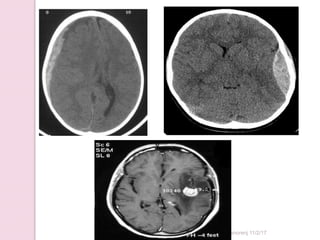

CT scan Brain SAH

Sandhya Manorenj 11/2/17

Hemorrhagic stroke

CT scan brain

• #33 SAH

• #36 SDH,EDH,Brain mets. subdural hematomas are classically crescent-shaped, with a concave surface away from the skull. However, they can have a convex appearance, especially in the early stage of bleeding.